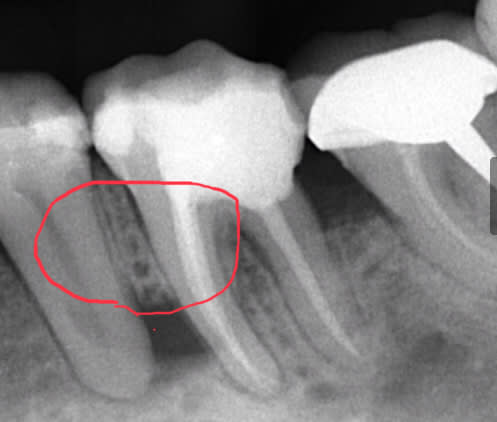

Et aujourd'hui, elle est contente plus aucune douleur sauf que en bouche je vois un bout d'os entre 35 et 36 et à la radio ... (image 3)

Outre le fait que je ne comprend pas trop ce que j'ai merdé, a votre avis c'est mort ou je tente de virer le fragment osseux de bien débrider et de voir ce qui se passe?

C’est le gros danger des intraligamentaires chez les fumeurs et aussi chez les diabétiques, nécrose osseuse due à un excès de vasoconstricteur sous pression.

a mon avis tu a glissé sous le périoste et tu l as disséqué sous pression .

Ca fait quand meme un gros morceau a enlever, c'est tout le septum qui a l'air de s'etre deplace vers le haut et qui donc serait mobile?

Tu as raison fatboy le morceau est important et je pense que la 5 et la 6 sont condamnées

on dirait que la nécrose soit partie de la prémolaire . comme si tu étais parti trop bas en vestibulaire de la molaire, et que tu aurais traversé l'os intra septal en direction de la prémolaire ..

si tu étais resté dans le ligament de la molaire la surpression serais repartie par l apex de la racine mésiale lors de l endo .